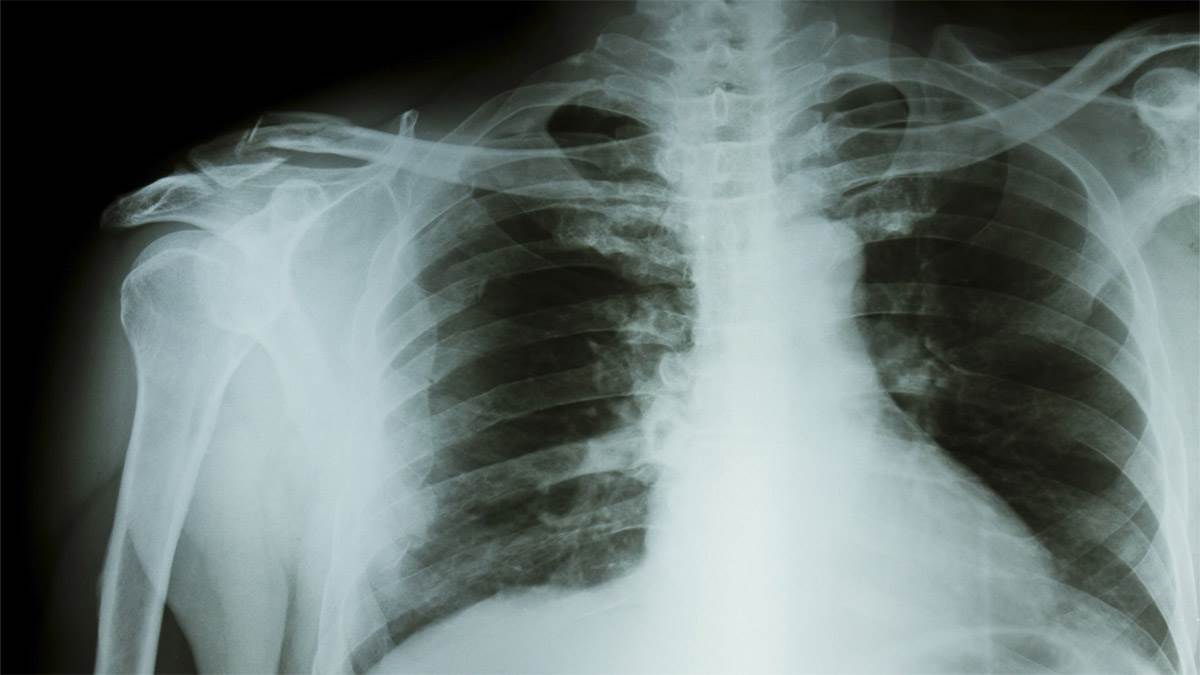

इस अभियान में एआई-सक्षम हैंडहेल्ड एक्स-रे, डिजिटल स्क्रीनिंग टूल, अपफ्रंट मॉलिक्यूलर डायग्नोस्टिक्स (एनएएटी) का इस्तेमाल किया गया और उच्च जोखिम वाले क्षेत्रों में पहुंच पर ध्यान केंद्रित किया गया। इस पहल के अंतर्गत 24.89 लाख मामले अधिसूचित किए गए, जिनमें से 8.7 लाख मामले लक्षणहीन थे। अधिकारियों ने बताया कि लक्षणों के बिगड़ने से पहले ही मामलों की पहचान करने से संक्रमण कम हुआ है और उपचार के बेहतर परिणाम मिले हैं, जिससे अंततः टीबी से संबंधित मौतों में कमी आई है।